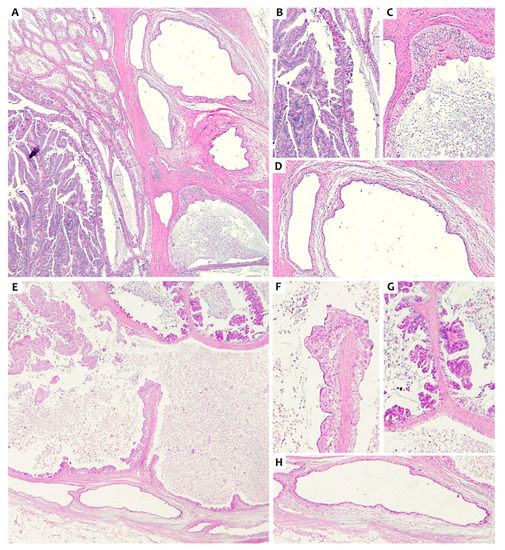

2. Presentation of Case #1

3. Presentation of Case #2